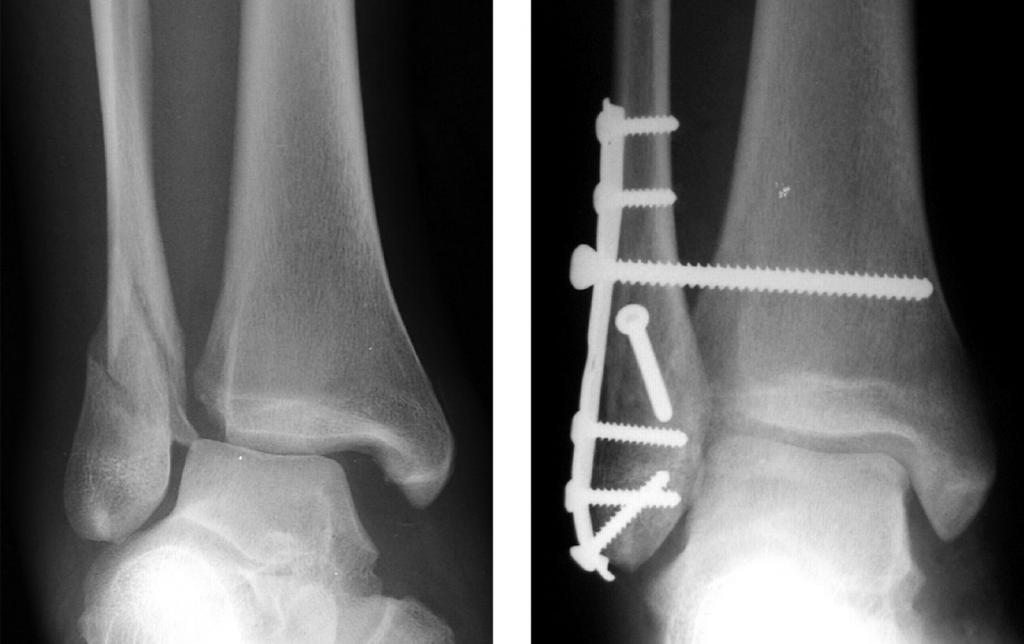

- Хирургический (сопряженный с проведением оперативных мероприятий). Его применяют при сложных открытых переломах или серьезных повреждениях со смещением осколков поврежденных костей, фиксацию которых производят с помощью специальных металлических спиц, штифтов, пластин, винтов и/или шурупов. Если после перелома лодыжки и удаления пластины болит нога, специалист назначает прием обезболивающих препаратов (в комплексе с другими реабилитационными мероприятиями). После эффективного сращивания сломанных костей металлические имплантаты полностью (или частично) удаляют.

После проведения операции на ногу накладывается гипс с открытым доступом к ране. Обязательно делают контрольную рентгенограмму.

Если применялись скрепляющие конструкции в виде болтов, штифтов, винтов, гвоздей, их удаляют спустя 4 – 6 месяцев, для чего требуется повторное оперативное вмешательство. Не удаляются титановые фиксаторы.